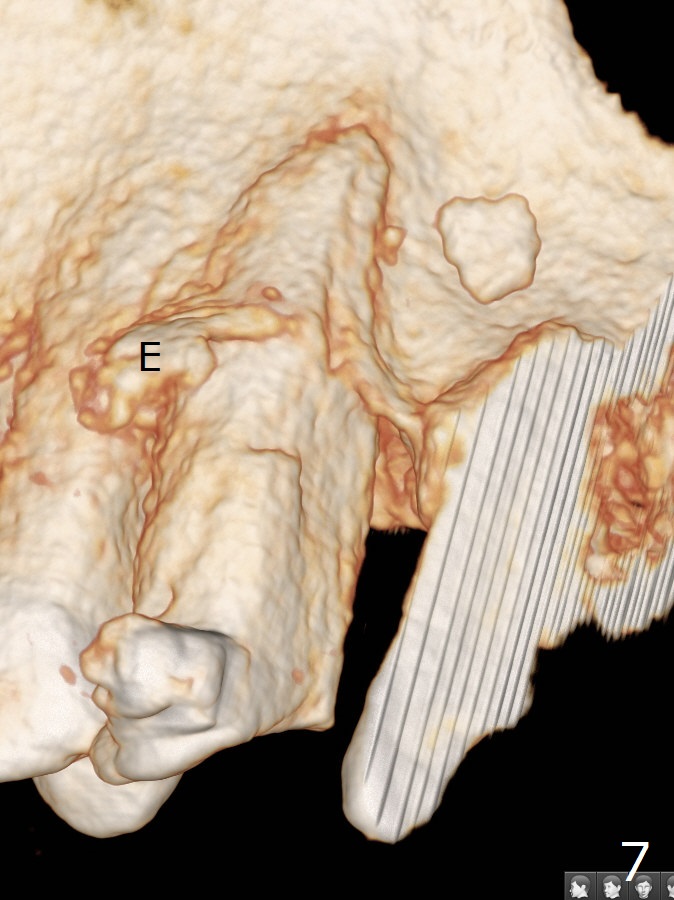

A 62-year-old man had traumatic root fracture at #6 in his teen. The tooth remained asymptomatic until his fifties. Following root canal therapy (Fig.1), the tooth is orthodontically extruded (~ 5 years, Fig.2 (*: bracket)) with apparent disappearance of the infection. The bone distal to #7 seems to increase in height (Fig.3, as compared to Fig.1) and in density (Fig.4). Bone graft could be placed for regeneration with PRF or GEM21S (Fig.5 red (between #6 and 7), pink (buccal to #7 or coronal to the fracture line) circles). With extrusion, the oblique fracture line is more than half or two third supragingival (Fig.6). In spite of severe bone loss, exostosis is present (Fig.7 (mesiobuccal view) E) so that bone graft could be placed palatal to it (Fig.8 red). In case the tooth is non-salvageable, immediate implant will be placed with guide (Fig.9,10). Move lingual button as apical as possible (Fig.12) and make occlusal clearance. Continue extrusion until all of the crack is exposed without deep pocket.